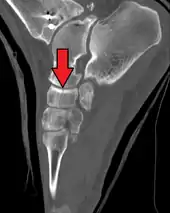

The human navicular is not a commonly broken bone but it breaks due two reasons. The first mechanism is a stress fracture which happens commonly in athletes [7] and the other mechanism is a high energy trauma. The navicular bone is a keystone of the foot: it is part of the coxa pedis and articulates with the talus, first, second and third cuneiform, cuboid and calcaneus. It plays an important role in the biomechanics of the foot helping in inversion, eversion and motion; it is a structural link between midfoot and forefoot and it is part of the longitudinal and transverse arch of the foot.